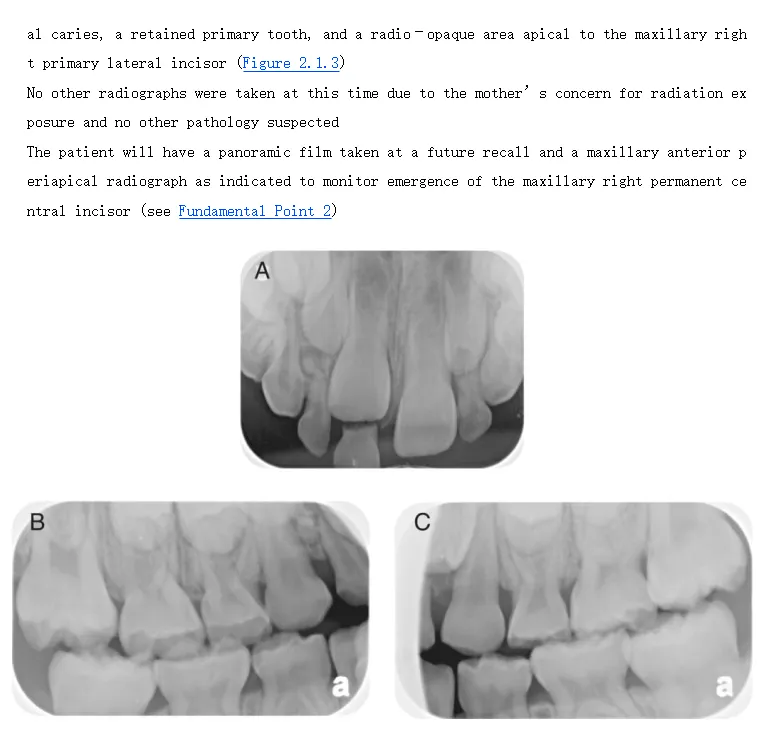

这本书对所有66个病例进行了全面更新,包括最新的诊断和治疗技术。 每章还包含全新的案件,总共13个全新案件。 所有病例均新增了最新的文献参考、最佳实践和循证临床指南,以及带有详细答案和解释的新自我评估问题。想要获取电子版《Clinical Cases in Pediatric Dentistry》,请关注公众号后,发送信息:“9781119290889”,稍等小编发送下载链接。